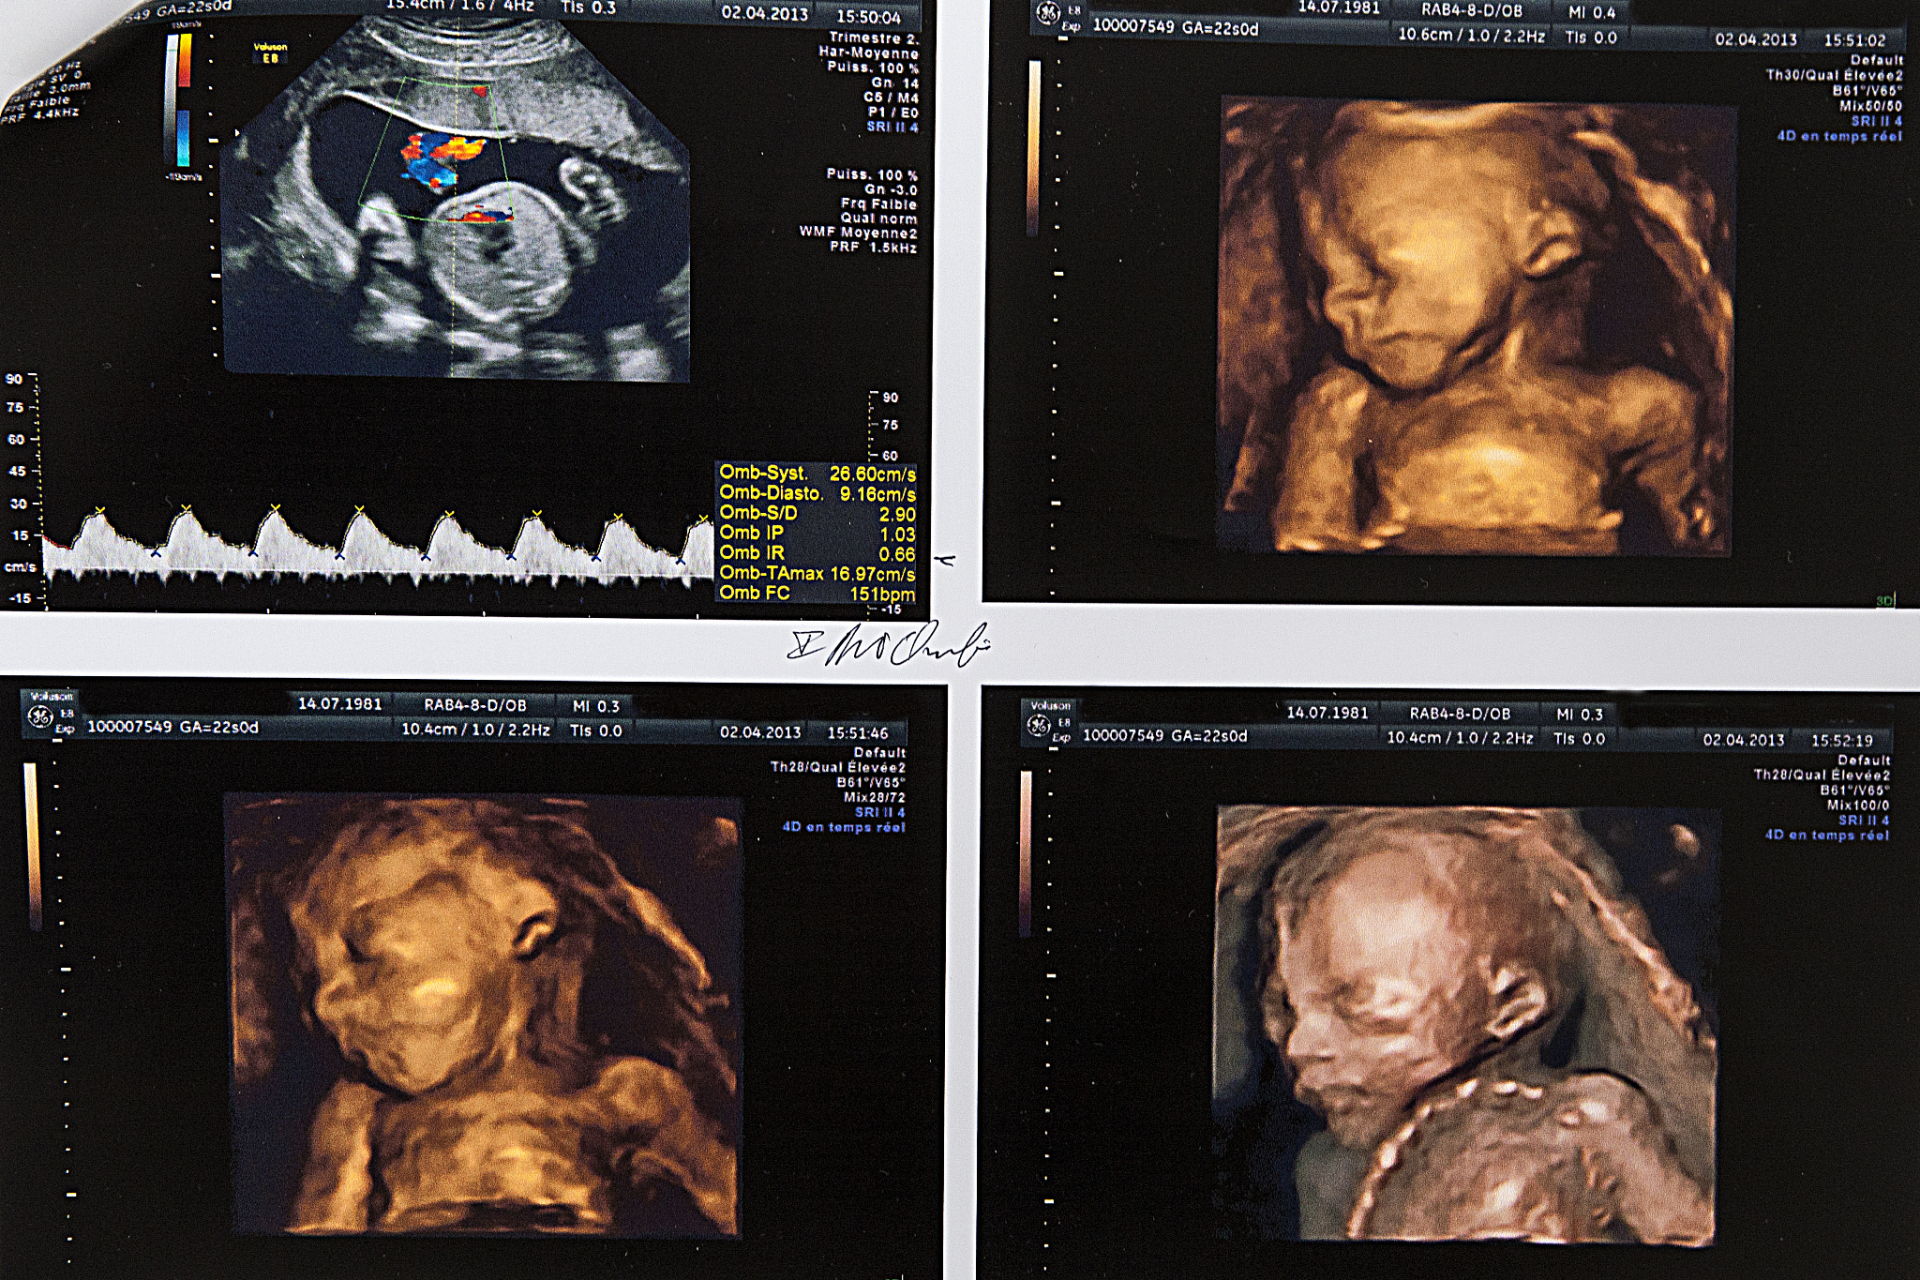

羊水正常! bpd双顶径hc头围ac腹围fl股骨颈!cdfl多普勒频谱仪!

附件:孕期bpd,ac,fl正常范围值股骨长度是胎儿大腿骨的长度,又称为"

腹围(ac)在超声脐静脉及门窦水平正位轴切面上,胃泡显示,肾脏不可见时